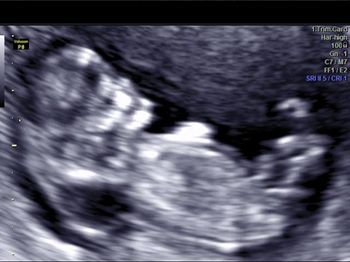

Challenge your diagnostic skills: Can you identify this well-known anomaly?